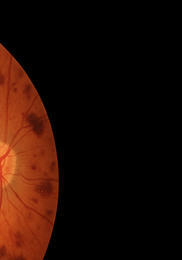

• 당뇨망막병증 – 모세혈관 누출로 혈액 성분이 유리체로 스며들며 거미줄 모양 혼탁이 나타납니다.

비문증 치료방법-비문증 원인